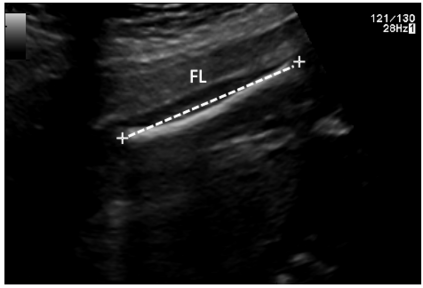

Deep-learning (DL) algorithms are becoming the standard for processing ultrasound (US) fetal images. Despite a large number of survey papers already present in this field, most of them are focusing on a broader area of medical-image analysis or not covering all fetal US DL applications. This paper surveys the most recent work in the field, with a total of 145 research papers published after 2017. Each paper is analyzed and commented on from both the methodology and application perspective. We categorized the papers in (i) fetal standard-plane detection, (ii) anatomical-structure analysis, and (iii) biometry parameter estimation. For each category, main limitations and open issues are presented. Summary tables are included to facilitate the comparison among the different approaches. Publicly-available datasets and performance metrics commonly used to assess algorithm performance are summarized, too. This paper ends with a critical summary of the current state of the art on DL algorithms for fetal US image analysis and a discussion on current challenges that have to be tackled by researchers working in the field to translate the research methodology into the actual clinical practice.